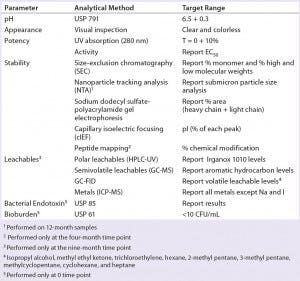

Table 2: Stability analytical methods

Stability: We used five different methods of testing product stability (Table 2). These include size-exclusion chromatographic and nanoparticle tracking analysis, sodium-dodecyl sulfate polyacrylamide gel electrophoresis (SDS-PAGE), capillary isoelectric focusing, and peptide mapping by ultraperformance liquid chromatography with UV and mass- spectrometric detection.